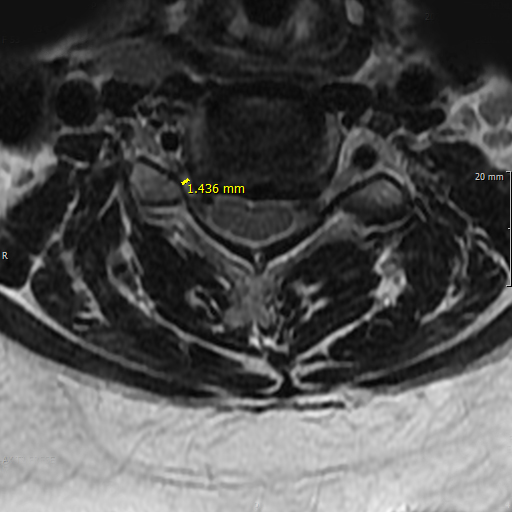

• 경추관협착증 진단

문진을 통해 환자의 증상 및 신체 기능을 확인하고 X-ray, MRI를 필수적으로 진행합니다.

경우에 따라 CT, 척수강조영술이 필요할 수 있습니다.